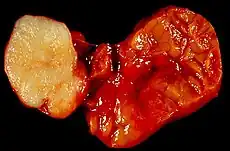

| Parotid gland tumour | |

Little is known about the total incidence of salivary gland tumours as most benign tumours go unrecorded in national cancer registries.[3] The majority of salivary tumours are benign (65-70%).[4] Within the parotid gland 75 - 80% of tumours are benign. Around 50% of the tumours found in the submandibular glands are benign. Sublingual gland tumours are very rare but if present, they are most likely to be malignant.[4][19] Saku et al. in 1997 [20] and Venturi [21][22] in 2021, reported the causal role for ionizing radiation in salivary gland tumorigenesis, particularly for mucoepidermoid carcinoma.